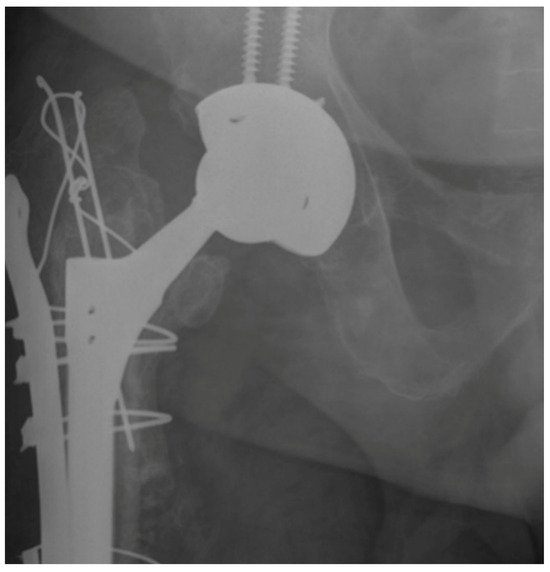

Comparison of Cylindrical and Tapered Stem Designs for Femoral Revision Hip Arthroplasty

2. Materials and Methods

2.2. Radiological Analysis